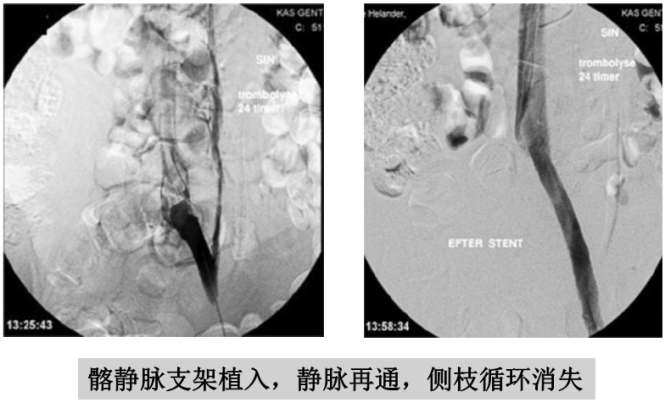

为了减少副损伤,同济医院血管外科组常规采取超声引导下穿刺腘静脉,造影后插入溶栓导管,术中和术后均经导管给药。如果发现髂静脉狭窄,可初步做球囊扩张,以增加效果。后续根据病人经济能力,以及溶栓效果,酌情考虑是否做髂静脉支架植入。

溶栓导管拔除前应做静脉造影,不仅可以判断溶栓效果,还可以发现和诊断髂静脉压迫综合征。髂静脉压迫综合征在正常人群中发生率约三分之一,在下肢深静脉血栓的病人中发生率较高。髂静脉压迫综合征一般发生在左侧,因为左侧髂静脉在生理上就位于右侧髂动脉和脊柱之间,很容易受压。这也是下肢深静脉血栓大多数发生在左侧下肢的原因。如果血栓没有完全溶解,且不准备接受髂静脉支架手术者,可以复查彩超后拔除导管。